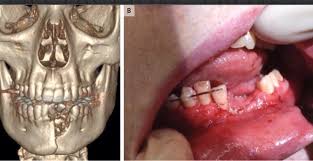

Thuốc lá điện tử nổ gây thương tích cho người hút

BS Huỳnh Hữu Dũng: Nguy cơ gần nhất là người sử dụng có thể bị chấn thương nghiêm trọng do nổ pin. Theo CDC Hoa Kỳ, từ năm 2009 - 2015, xảy ra 92 vụ cháy, nổ do TLĐT, gây chấn thương ở 47 người và thiệt hại tài sản. Còn ở Anh thì ghi nhận hơn 100 vụ cháy, nổ; 4 trường hợp tử vong do cháy, nổ từ TLĐT.